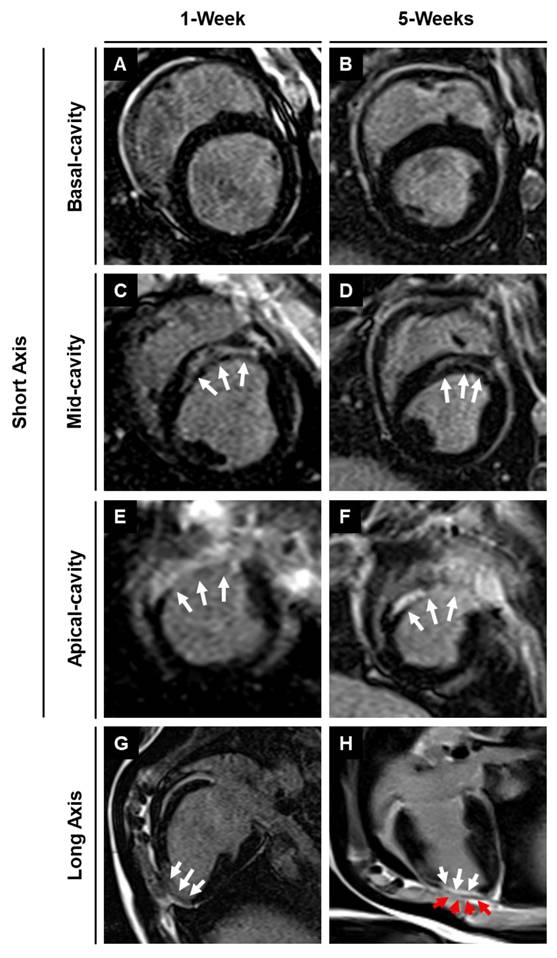

3.5. Assessment of infarction using magnetic resonance imaging with late gadolinium enhancement

Late gadolinium enhancement imaging was used to identify the location and extent of cardiac fibrosis in the infarcted area and subsequent scar tissue remodeling over 5-weeks post-MI. LGE imaging along the long axis showed the location of the transplanted patch appearing as dark epicardial hypointense area, and the area of infarct which appeared as an area of hyper-enhanced myocardium (Fig. 6). LGE imaging along the short axis demonstrated the localization of the infarct region at the anteroseptal wall in the mid and apical regions, revealing an epicardial/mid-wall pattern of LGE consistent with non-transmural infarction (Fig. 6). Furthermore, quantitative assessment showed a 28.8% reduction in infarct size by 5-weeks post-MI in pigs treated with the cardiac patch. In contrast, pigs that did not receive the cardiac patch (control group) exhibited a slight decrease in infarct size by 18.6%. While the reduction in infarct size in the pigs that received the cardiac patch transplant was higher than the control animals, the difference was not statistically significant between the two groups. We observed a slightly higher decrease in enhancement percentage in the MI + patch group, indicating a smaller region of fibrosis in these animals compared to the MI-only group.

Figure 6

MRI-LGE images showing the site of patch transplantation on the pig heart. Representative LGE images along the (A-F) short and (G-H) long axis at 1- and 5-weeks post-MI in MI + Patch group. White arrows are pointing towards the hyper enhanced infarcted region involving the left ventricular apical wall and interventricular septum. Red arrows are pointing towards the transplanted epicardial patch over the infarcted region (dark area on LGE imaging) (H).